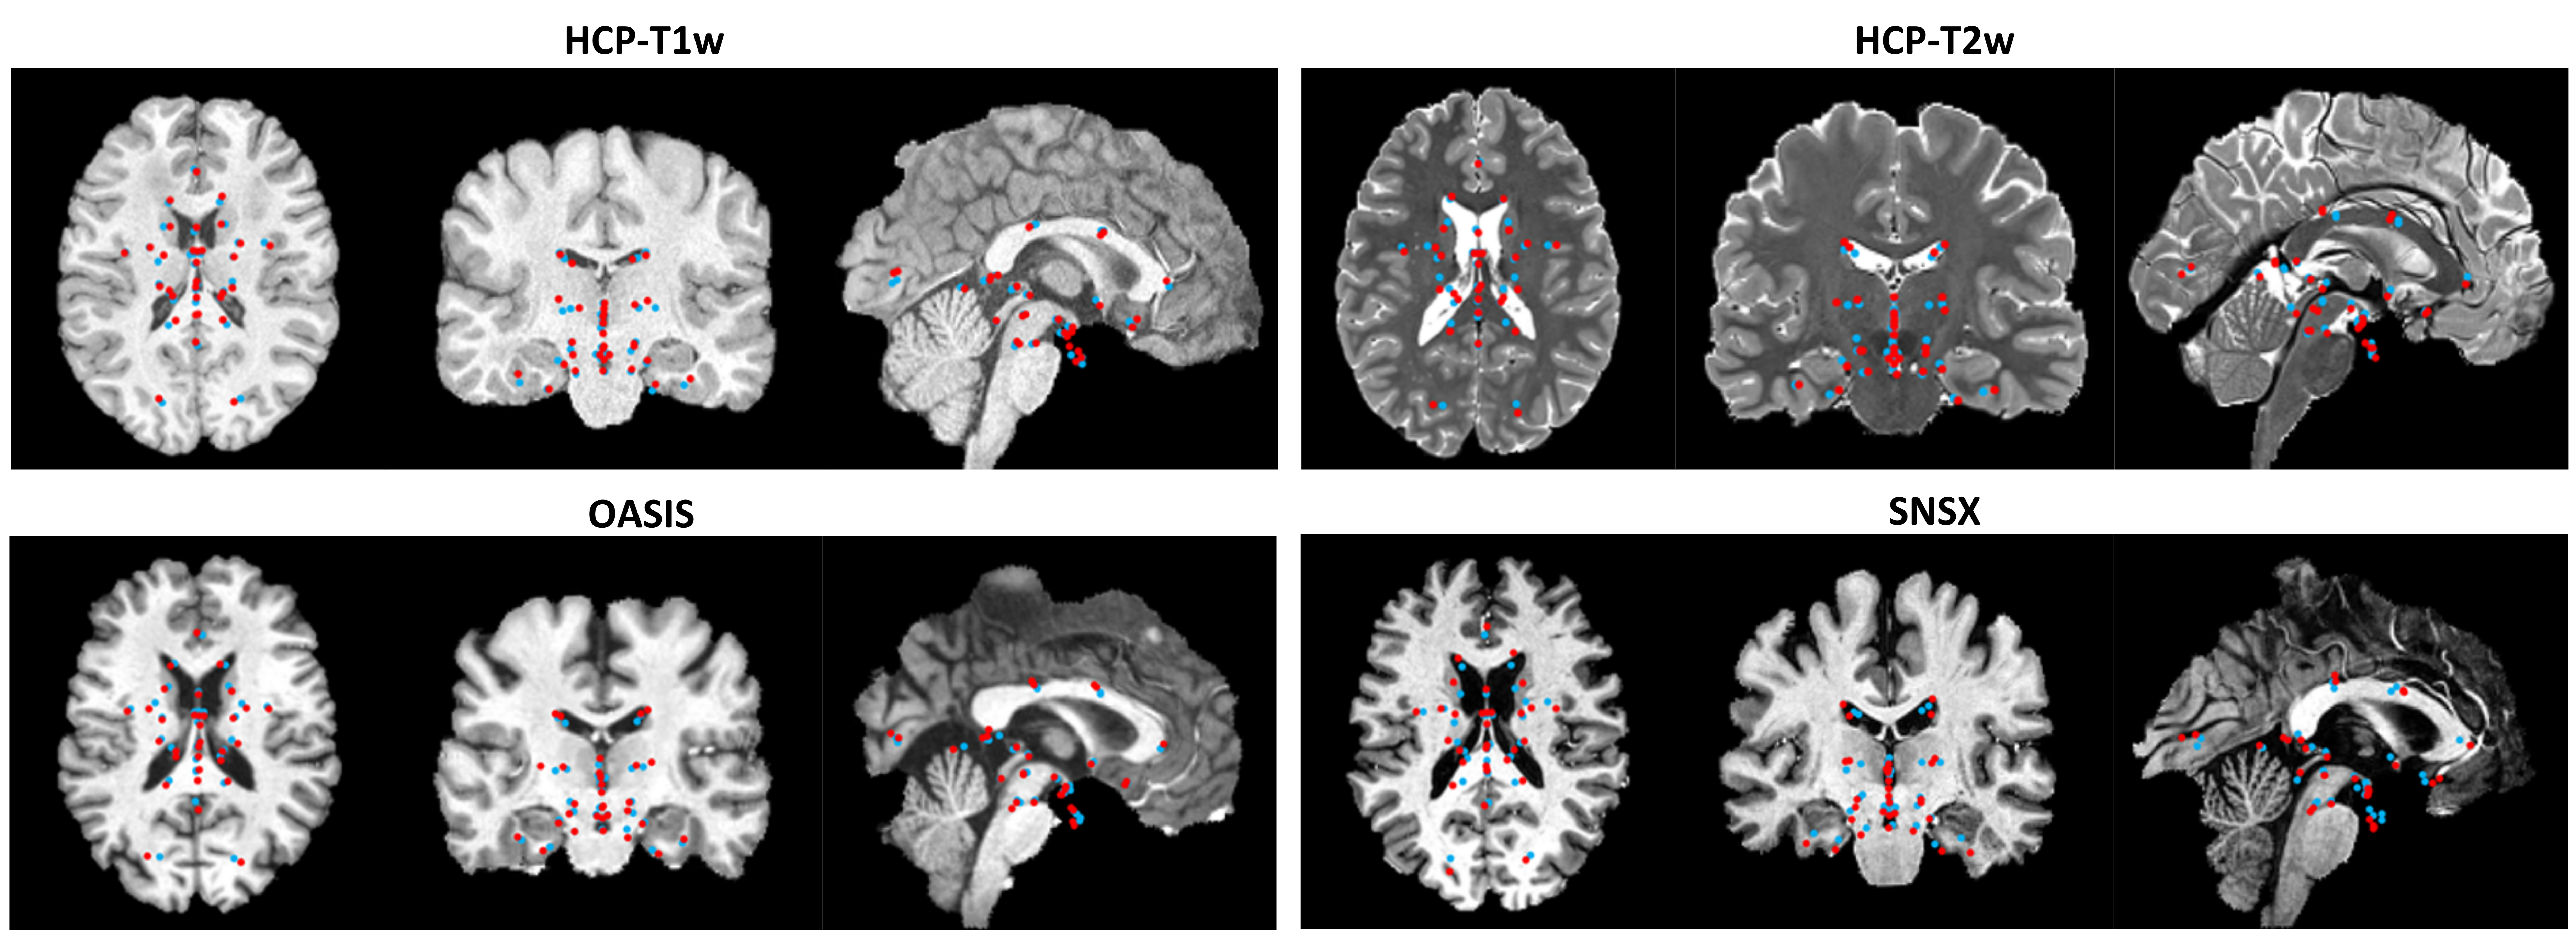

To check if CABLD can generalize on other MRI contrasts, we evaluated it on the HCP T2w dataset. Table 2 shows the results of different models on the HCP T2w dataset. Although our model has only been trained on T1w scans, we can see that it could outperform the other baseline methods on the T2w scans. Specifically, CABLD achieved an MRE of 3.99 ± 2.25 mm, which is comparable to the best-performing method, ANTs (MI), at 3.91 ± 2.19mm. Notably, CABLD attained the highest SDR at the 6mm (86.43%) and 9mm (98.99%) thresholds, surpassing all other methods. While its SDR at the 3 mm threshold (27.19%) was slightly lower than that of ANTs (MI) (35.00%) and MultiGradICON (33.33%), CABLD still demonstrated strong performance, given it was not trained on T2w images. Figure. 2 illustrates a few sample of the CABLD results.

Refer to caption

Figure 2: Qualitative comparison of anatomical landmark detection results using the proposed technique, illustrated on coronal, axial, and sagittal mid-slices (red=ground truths, blue=automatic results) for samples across all datasets. Note that the landmarks are shown as projections of 3D points in each canonical view for visual demonstration purposes only.